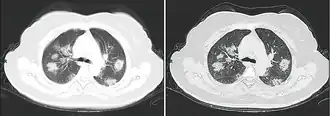

Tomografia computadorizada do tórax

Às vezes, tomografias computadorizadas (TC) do tórax podem ajudar a identificar e caracterizar o estado patológico pulmonar e produzir achados inespecíficos com a infecção por COVID-19. Um estudo descobriu que a sensibilidade da tomografia computadorizada para infecção por COVID-19 era de 98%, em comparação com a sensibilidade da RT-PCR de 71%. No entanto, o teste foi realizado em Wuhan, na China, e, por isso, pode não ser generalizado.[25][26] Grande parte dos achados consistia na presença de opacificação em vidro fosco na região subpleural e pavimentação em mosaico. Esses achados são inespecíficos, pois também são encontrados em outros tipos de pneumonia. Nenhum estudo avaliou, ainda, a precisão e o valor discriminatório das tomografias para distinguir a COVID de outras pneumonias virais.[27][28]

Achados típicos através da TC

Achados típicos através da TC Progressão de achado através de TC

Progressão de achado através de TC